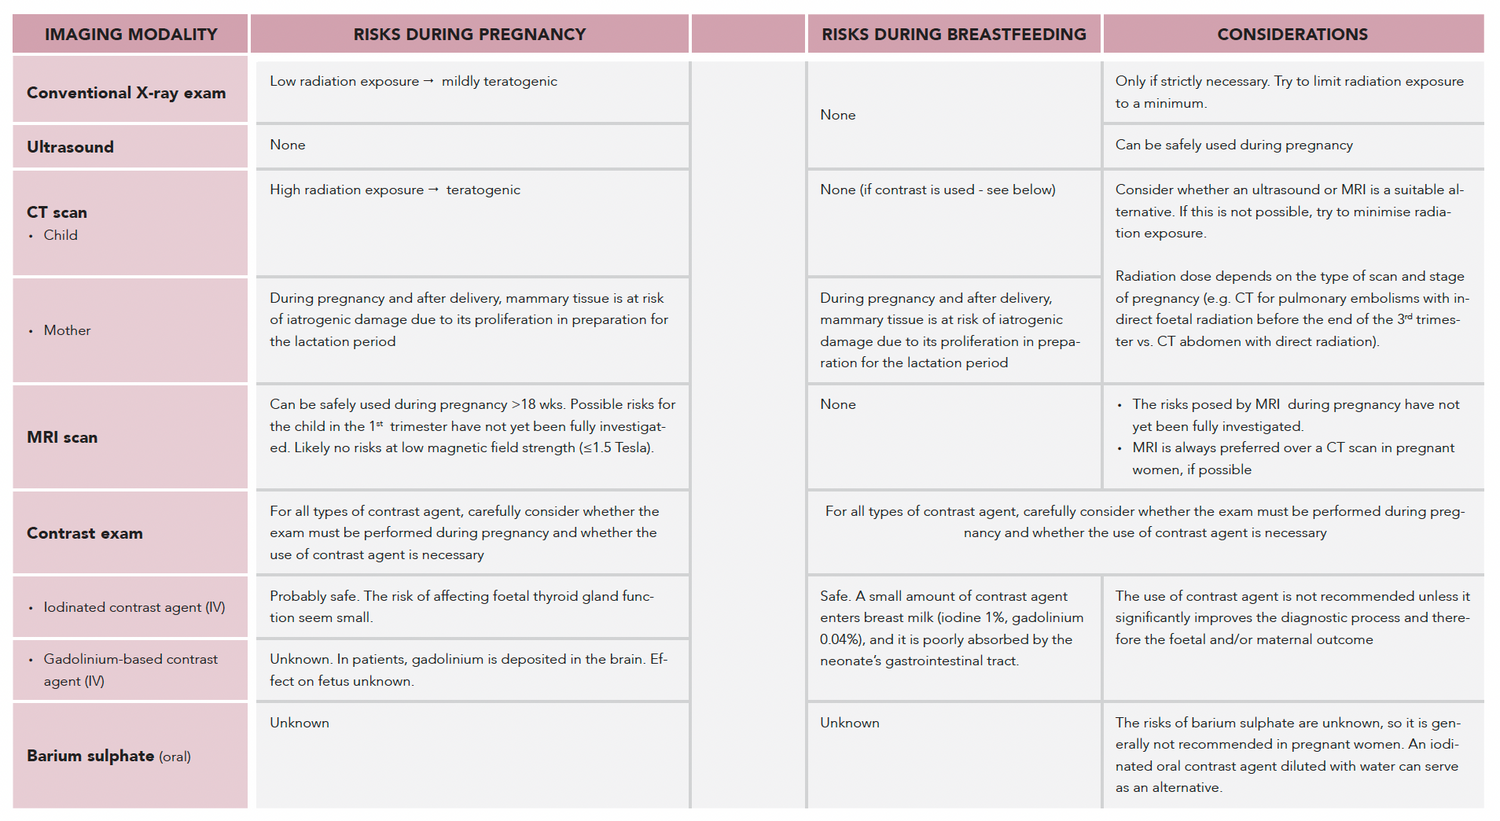

Tables to present information clearly